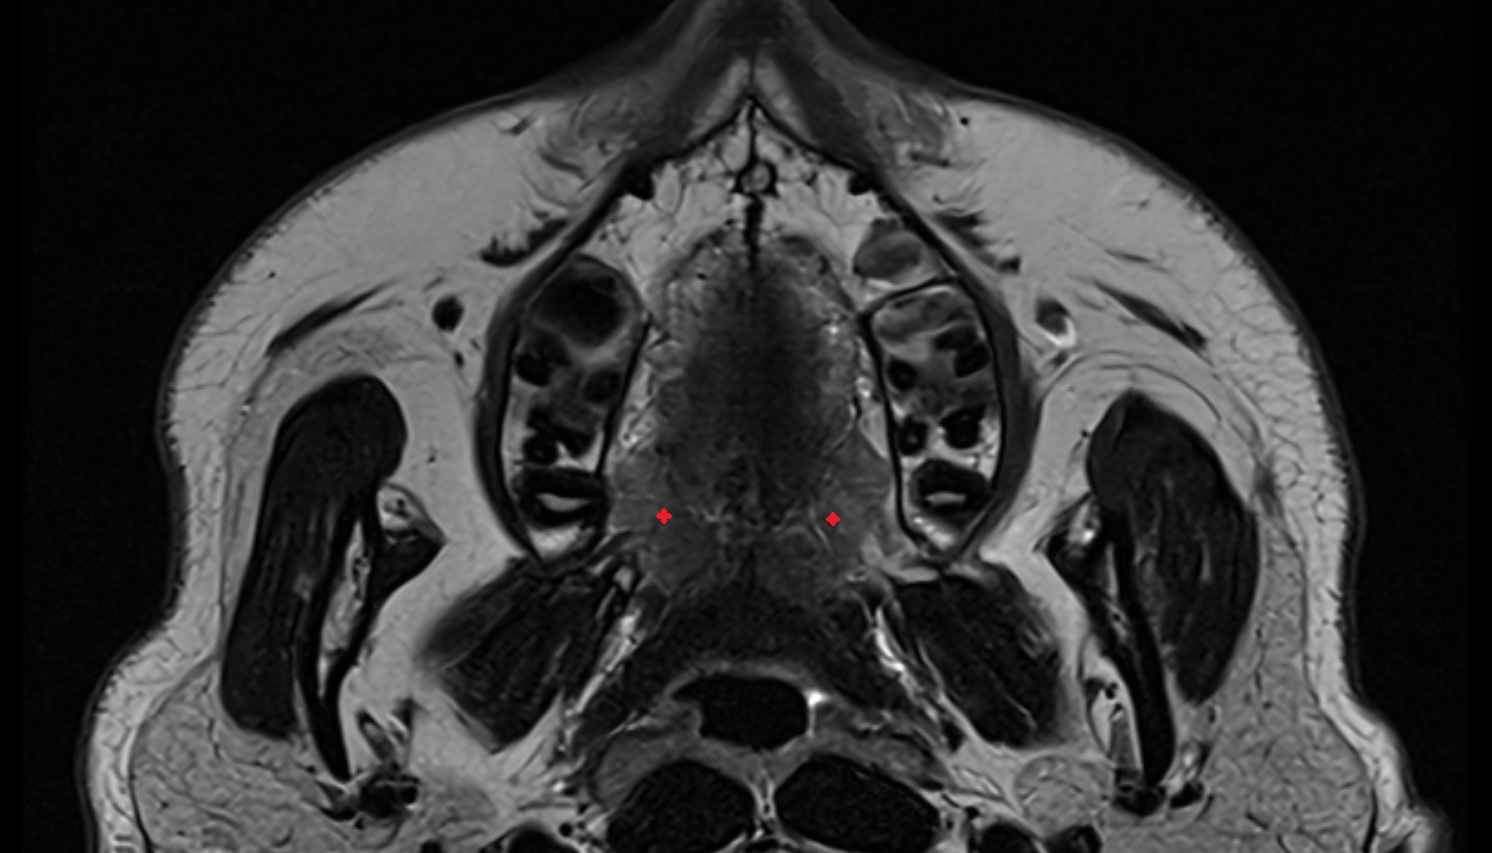

- Hippocampus

- Body of hippocampus

- Head of hippocampus

- Tail of hippocampus